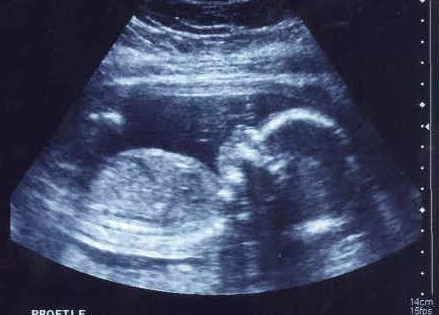

孕酮是孕激素的一種,是孕期檢查的重要數值之一,對于生育的生理作用是毋庸置疑的,孕早期往往有很多孕婦檢查到孕酮低,那么孕酮低是先兆流產的指標嗎?可作為流產依據嗎?下面八寶網帶來介紹。

既往的研究證明,孕酮對于生育的生理作用是毋庸置疑的。孕酮可以維持懷孕早期八周以內的胚胎發育。正因如此,不少醫生特別喜歡檢查孕酮。監測早孕期的孕酮水平,是因為懼怕流產,擔心是因為缺少孕酮造成妊娠丟失,然而孕酮低就預示著即將流產嗎?